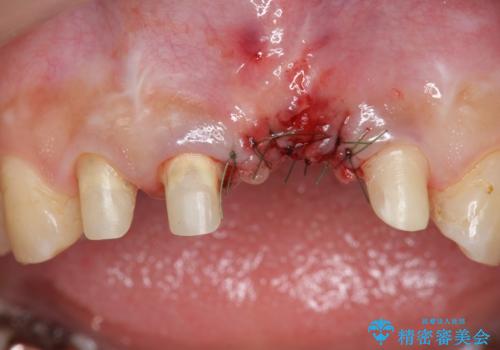

不良インプラントを除去し最終的にブリッジによる補綴で審美性の改善を行うこと、その準備として骨の造成・歯肉の移植による歯の欠損部顎堤のボリュームを維持・増大を計画します。

より審美的な改善を強く求められたため、インプラントを除去し可及的に欠損部顎堤を増大したのちブリッジによる審美改善を行いました。